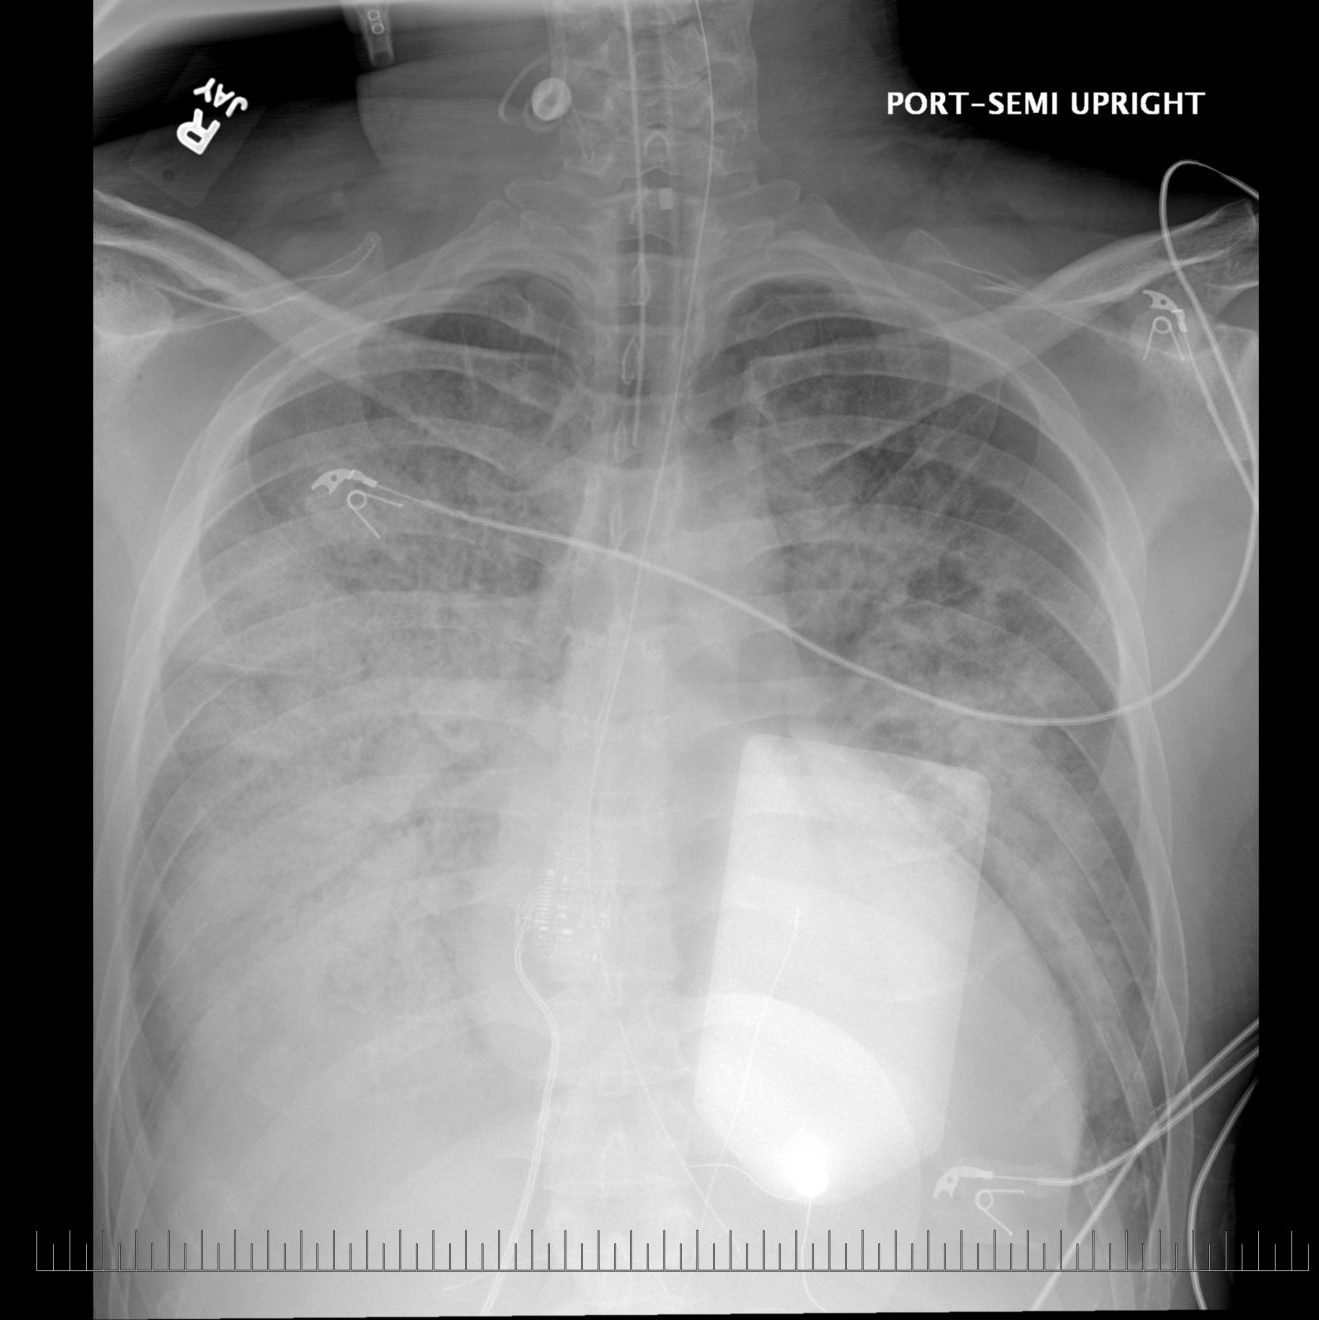

They told me that my heart had enlarged to 1.5 times the normal size and that I had ventricular tachycardia (Vtach) – a condition where the heart gets into a dangerous, potentially fatal, rhythm. At the time they didn’t really know how I got the condition or what the treatment for me would be yet, but they did know that I needed something to protect me from going into that dangerous rhythm again, because if I did my heart would not be able to take it. So before I left the hospital they needed to perform a surgery to implant a device to protect me from future episodes of Vtach – an ICD (implantable cardioverter defibrillator) that is wired to my heart and would essentially send a shock to my heart to get it back into a normal rhythm. And because I’ve had it all my life, my heart has become weak, really weak. It pumps out less than half as much blood as a healthy heart. I’m technically living in a state of heart failure.